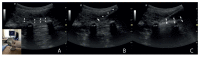

Methods: Ultrasound-guided lumbar ESPB was performed in three formaldehyde-embalmed human cadavers. For this purpose, a 10 mL of methylene blue was injected into the fascial space between the L4 transverse process and the erector spinae muscles. T hen, the cadavers were dissected, the cephalocaudal and lateral spread of the dye was examined, and the involvement of the dorsal rami, dorsal root ganglia and ventral rami were analyzed. The distribution into the epidural space was also evaluated.